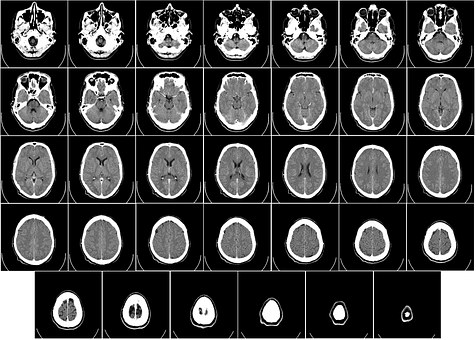

Entre las estructuras cerebrales implicadas en la conciencia se incluyen, fundamentalmente, el sistema reticular activador, el tálamo, los ganglios basales o la corteza cerebral para los procesos más básicos y, la corteza prefrontal medial y orbitofrontal (así como las conexiones que establece con otras regiones corticales) o el sistema límbico para los procesos más complejos de la conciencia. Por tanto, neuroanatómicamente, la conciencia no es más que un sistema de redes que establece relaciones entre diferentes regiones cerebrales.